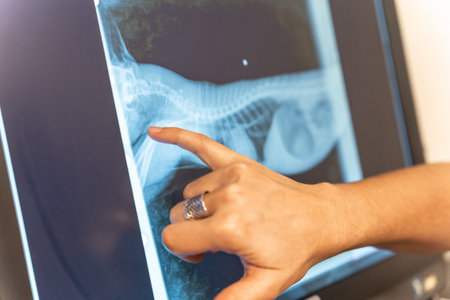

The male hand of the dentist on the monitor screen shows the jaw.

The male hand of the dentist on the monitor screen shows the jaw.

Veterinary clinic, veterinarian reviewing the x-ray of the dog to be treated on the computer